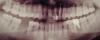

FIRE Опубликовано 21 января, 2011 Автор Поделиться Опубликовано 21 января, 2011 Все Вы так поняли. Необходимо распломбировать канал, прочистить и адекватно его запломбировать.Спасибо. Скажите, а по снимку ещё какие-нибудь зубы нужно делать? кроме нижней шестёрки, я её удалил. Ссылка на комментарий

vicvil Опубликовано 21 января, 2011 Поделиться Опубликовано 21 января, 2011 мне не очень нравится пломба на соседнем центральном резце... Ссылка на комментарий

Alexandr dantist Опубликовано 21 января, 2011 Поделиться Опубликовано 21 января, 2011 Спасибо. Скажите, а по снимку ещё какие-нибудь зубы нужно делать? кроме нижней шестёрки, я её удалил. Соседний стоит перелечить, покрыть коронкой. С той же стороны сделать прицельный снимок 6 снизу, поставить диагноз,лечить. 6 с противоположной стороны возместить(спротезировать). Это все, что можно сказать по снимку. Более детально вам расскажет врач, который вас осмотрит. P.S. не тяните с протезированием. Ссылка на комментарий